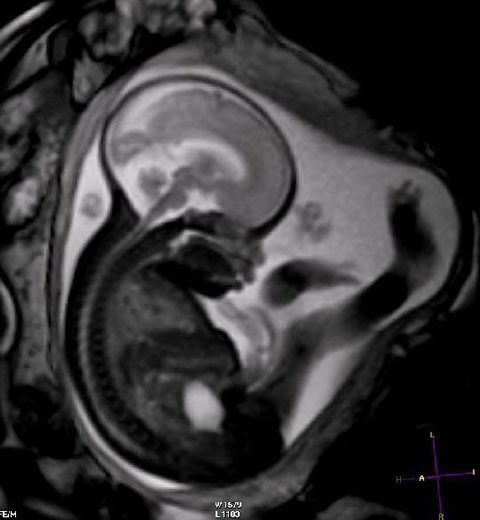

Resultados tras cuatro años de detección del cáncer de próstata con PSA y resonancia magnética

08 octubre 2024

En este ensayo, la omisión de la biopsia en pacientes con resultados negativos en la resonancia magnética eliminó más de la mitad de los diagnósticos de cáncer de próstata clínicamente insignificante, y el riesgo asociado de tener un cáncer incurable diagnosticado en la detección o como cáncer de intervalo fue muy bajo.   N Engl J Med 26 de septiembre de 2024